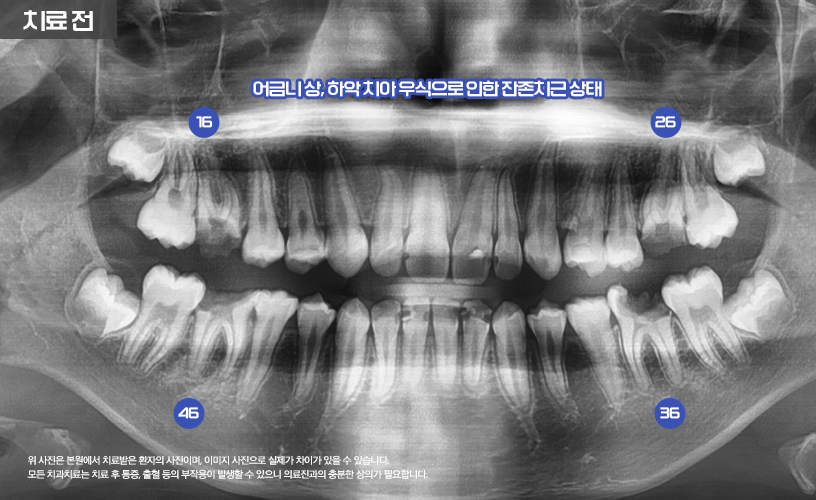

상기 환자분은 23년도에 본 원에서

치료한 사례입니다.

환자분의 연령의 경우 그 당시에 12세 환자로

오랜 외국 생활로 인해 치과치료를 제때 받지 못하여

충치가 매우 심각한 상태였습니다.

나머지 상, 하악 16,26,36,46번 치아는

신경치료를 통해 치료가 진행됩니다.